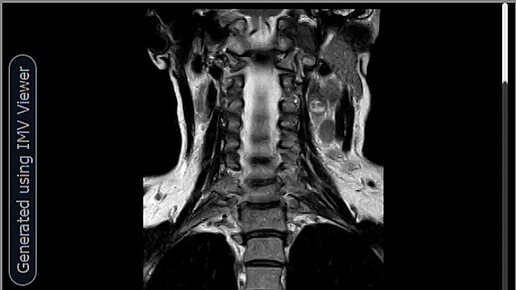

МРТ-Метастазы в лимфоузлы шеи